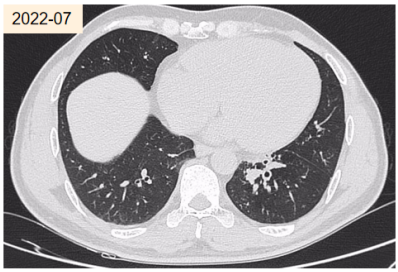

患者,女性,60岁,主因「反复气喘50余年,加重伴胸闷胸痛2周」于2021年7月28日由胸外科医生转介至我科。既往有哮喘、真菌性鼻窦炎。白细胞7.97×10^9/L,嗜酸粒细胞比值18.6%,T-lgE 558.39 IU/ml(正常值1.27~241.3 IU/ml);m3(烟曲霉)0.71 kUA/L(正常值<0.35);影像学可见痰栓。

abp在医学是什么意思2021日本ABPA/ABPM诊断标准解读_https://www.jmylbn.com_新闻资讯_第12张

虽然血清中IgE并未达到1000 IU/ml,但其他标准都符合!最终诊断为ABPA,支气管哮喘。